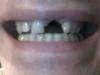

Cave Опубликовано 14 марта, 2010 Автор Поделиться Опубликовано 14 марта, 2010 А фото во рту можно увидеть? такое впечатление, что расстояние между 11 и 22 зубом очень широкое Да, оно довольно большое. Фото прикрепляю.На идеальную эстетику я уже и не расчитываю ( Ссылка на комментарий

pawa Опубликовано 14 марта, 2010 Поделиться Опубликовано 14 марта, 2010 (изменено) Люди, ну черкните хоть что нибудь дельное!А фото во рту можно увидеть? такое впечатление, что расстояние между 11 и 22 зубом очень широкое Изменено 14 марта, 2010 пользователем pawa Ссылка на комментарий